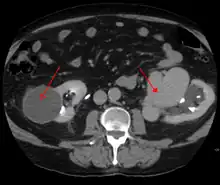

AVMs are diagnosed primarily by the following imaging methods:[12]

- Computerized tomography (CT) scan is a noninvasive X-ray to view the anatomical structures within the brain to detect blood in or around the brain. A newer technology called CT angiography involves the injection of contrast into the blood stream to view the arteries of the brain. This type of test provides the best pictures of blood vessels through angiography and soft tissues through CT.

- Magnetic resonance imaging (MRI) scan is a noninvasive test, which uses a magnetic field and radio-frequency waves to give a detailed view of the soft tissues of the brain.

- Magnetic resonance angiography (MRA) – scans created using magnetic resonance imaging to specifically image the blood vessels and structures of the brain. A magnetic resonance angiogram can be an invasive procedure, involving the introduction of contrast dyes (e.g., gadolinium MR contrast agents) into the vasculature (circulatory system) of a patient using a catheter inserted into an artery and passed through the blood vessels to the brain. Once the catheter is in place, the contrast dye is injected into the bloodstream and the MR images are taken. Additionally or alternatively, flow-dependent or other contrast-free magnetic resonance imaging techniques can be used to determine the location and other properties of the vasculature.